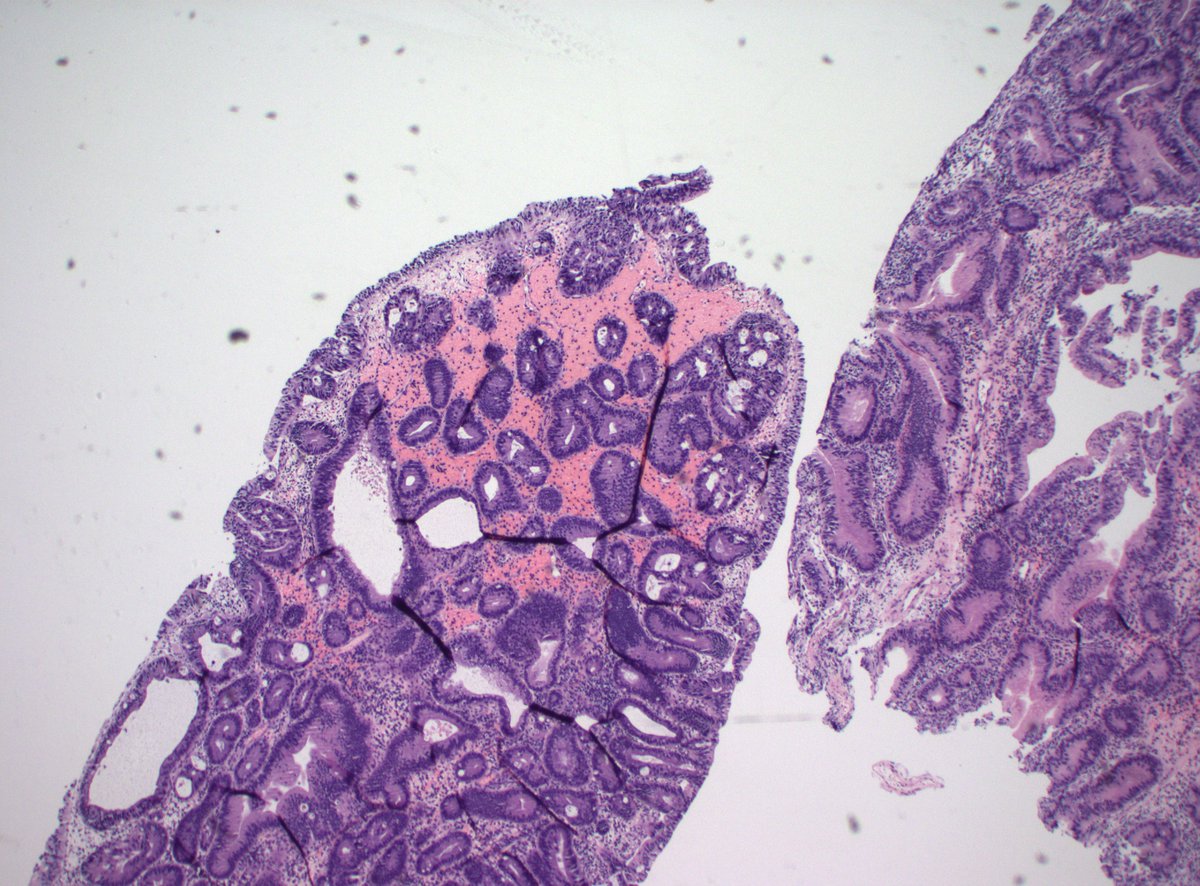

This was a curbside consult from #dermpath. Patient has a history of mastectomy for breast cancer and is now presenting with a chest wall skin nodule. What is your diagnosis? - IHC: p63 @wusm_pathology WashU Medicine Pathology & Immunology Education #breastpath #PathTwitter #PathX

Happy Monday everyone! This is an incidental finding in a reduction mammoplasty. What is your diagnosis? #breastpath #PathTwitter WashU Medicine Pathology & Immunology WashU Medicine Pathology & Immunology Education